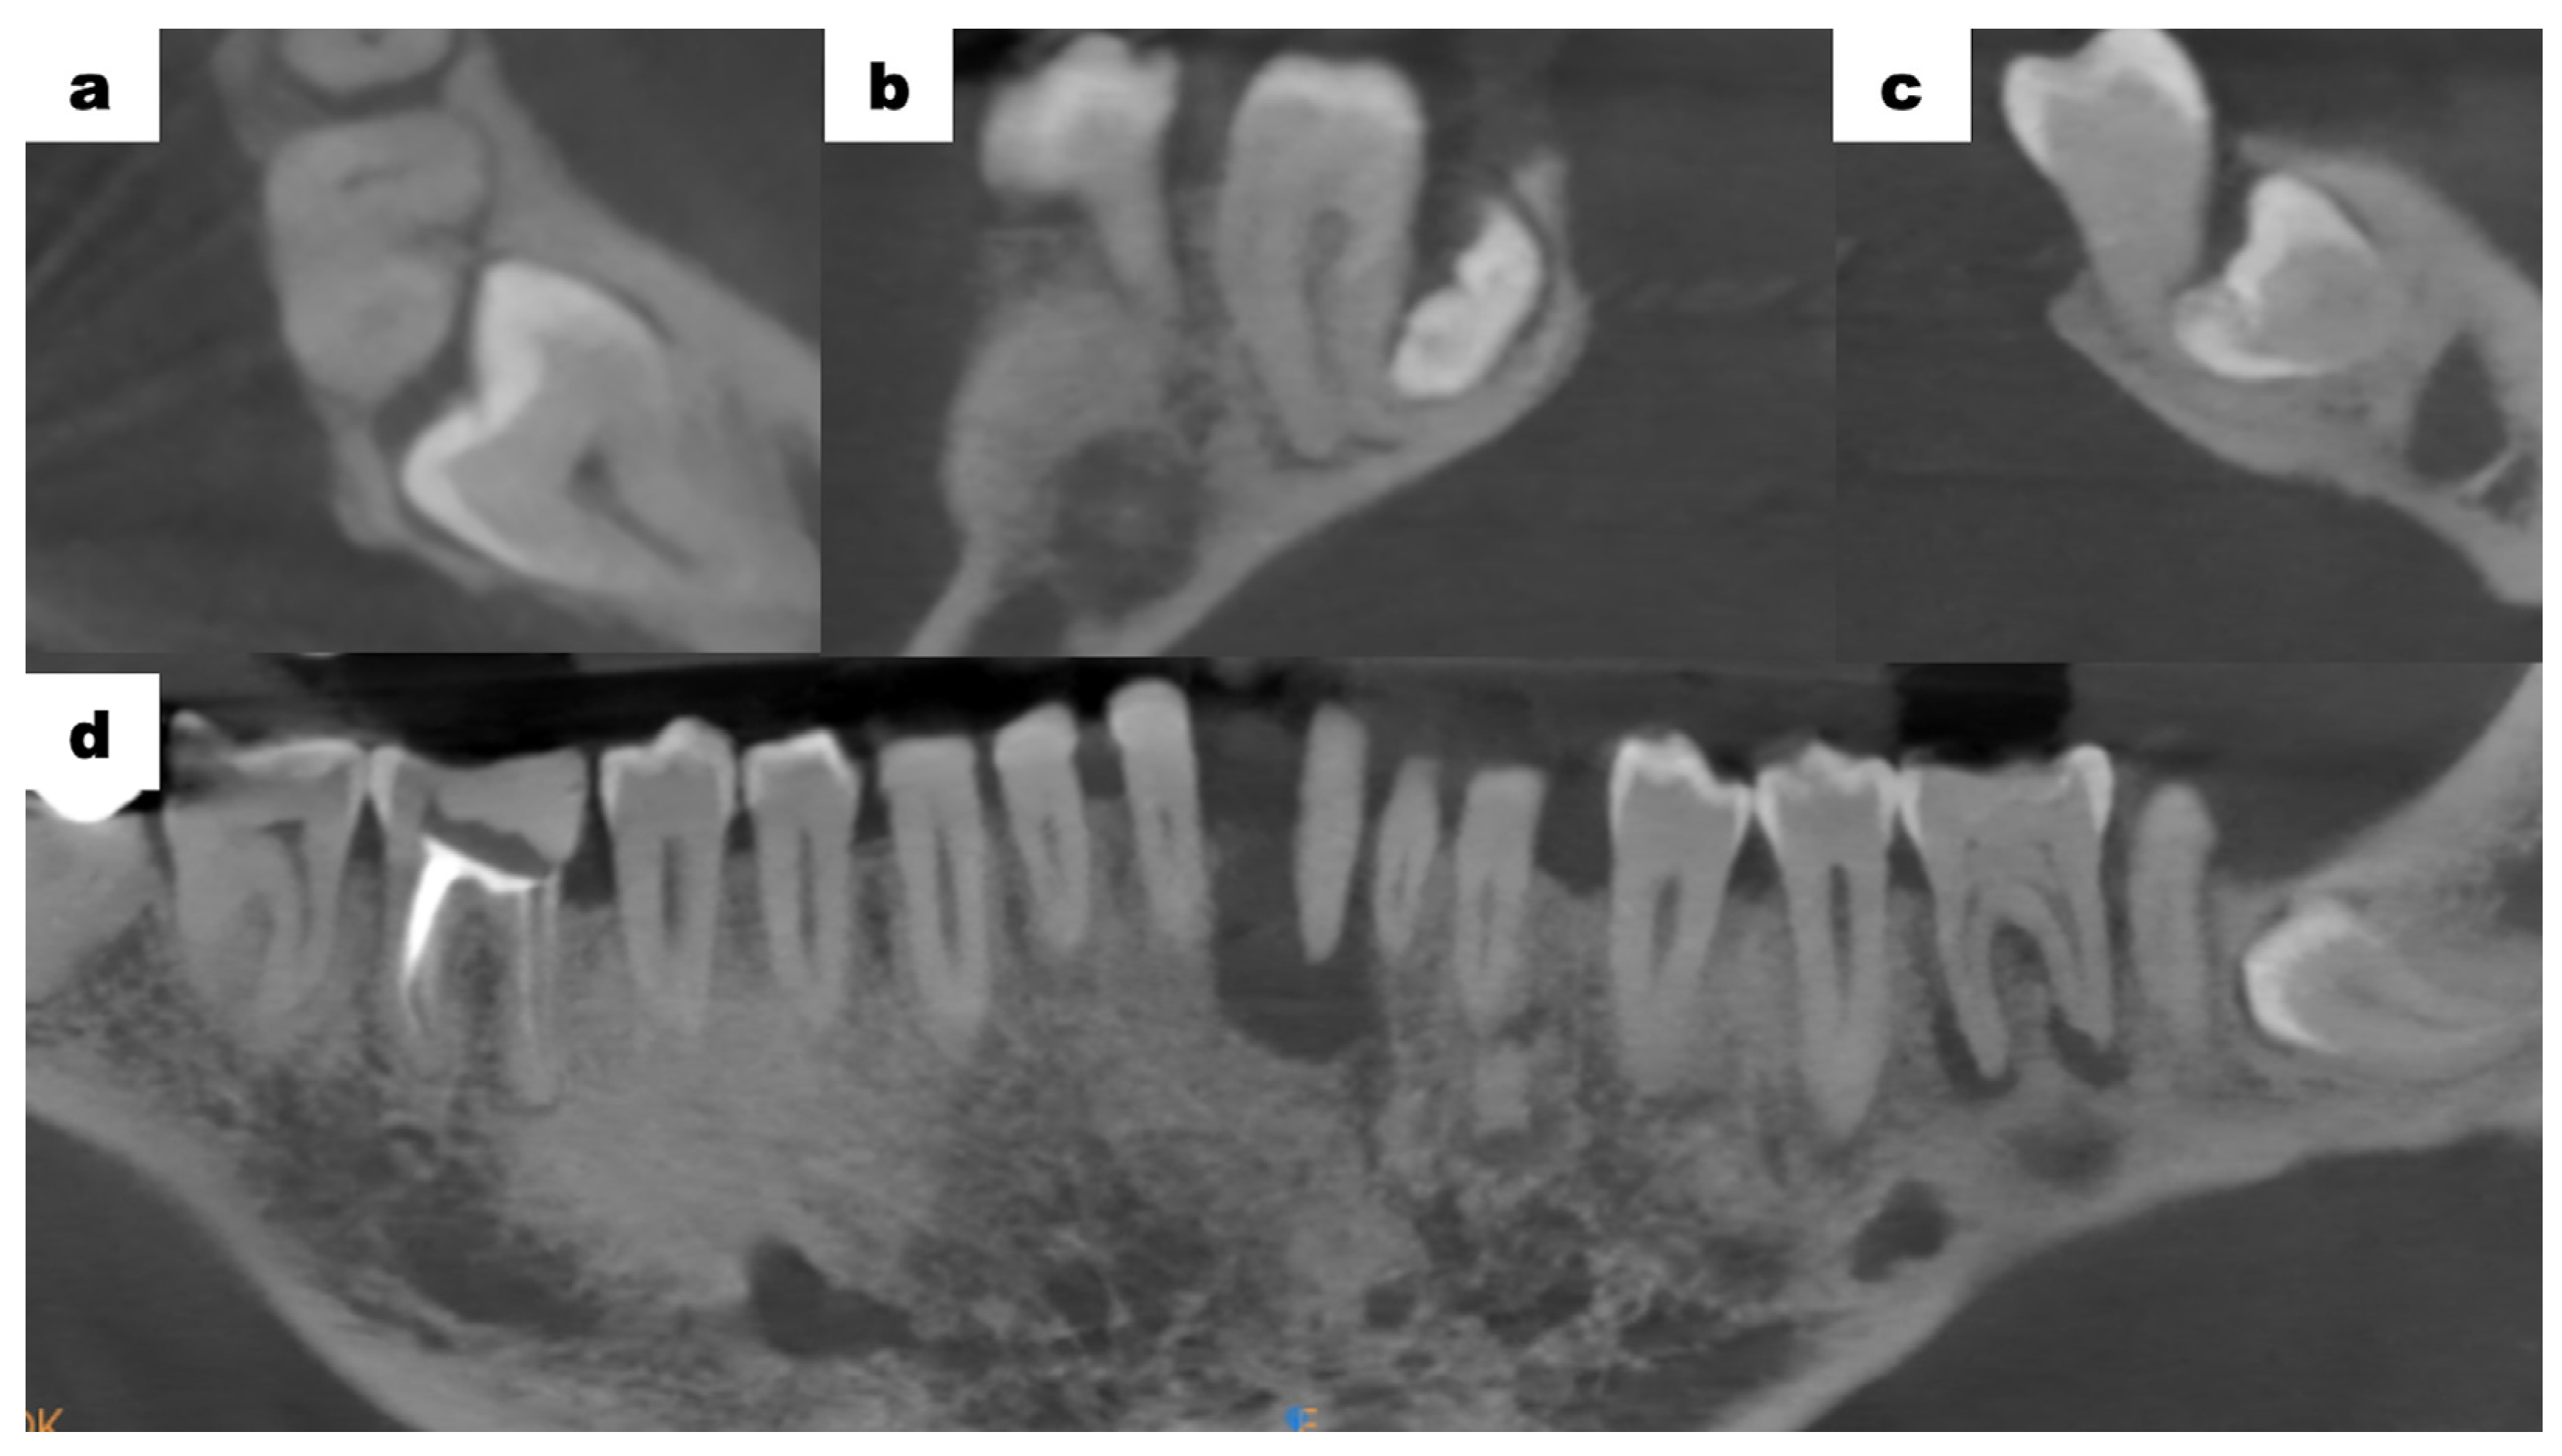

Cone-beam computed tomography (CBCT—cone-beam computed tomography) scans of the mandible, which were provided by the patient, revealed bone resorption around tooth 31. The lateral surfaces of the apices of teeth 41 and 32 were adjacent to the periapical lesion of tooth 31 (Figure 3a). Tooth 46 was treated endodontically for a deficiency of filling material in the apical region of the roots (Figure 3b). Tooth 47 showed a carious lesion. Tooth 36 exhibited extensive periapical changes (Figure 3c). Tooth 38 was partially retained in the horizontal, mesial-angular position with no eruption potential. No inflammatory cysts were found around the crown of the retained tooth. There were no signs of resorption of tooth 37 (Figure 4a). However, the distal root surface of tooth 37 was exposed due to the adjacent position of tooth 38, enabling plaque retention. This might be a potential source of inflammation (Figure 4b). In the event of peri-coronal inflammation, tooth 38 will be eligible for an extraction in the hospital setting. CBCT scans revealed areas of bone thinning in the chin region, potentially due to irradiation treatment when the patient was at the developmental age (Figure 4c).

Figure 3.

CBCT examination scans before initiation of treatment; (a) tooth 31—inflammatory change involving the entire root; (b) tooth 46—no trace of filling material in the root canals in the apical region, a suspected periapical lesion; (c) tooth 36—periapical inflammatory changes visible around both roots.

Mandibular CBCT examination scans before initiation of treatment; (a) an axial plane scan—tooth 38 retained in the horizontal, mesial-angular position; (b) a sagittal plane scan—tooth 37 distally exposed due to the adjacent position of tooth 38, no signs of root resorption; (c) a frontal plane scan—between tooth 37 and 38, visible potential plaque retention; (d) anteroposterior projection—bone thinning in the chin region.